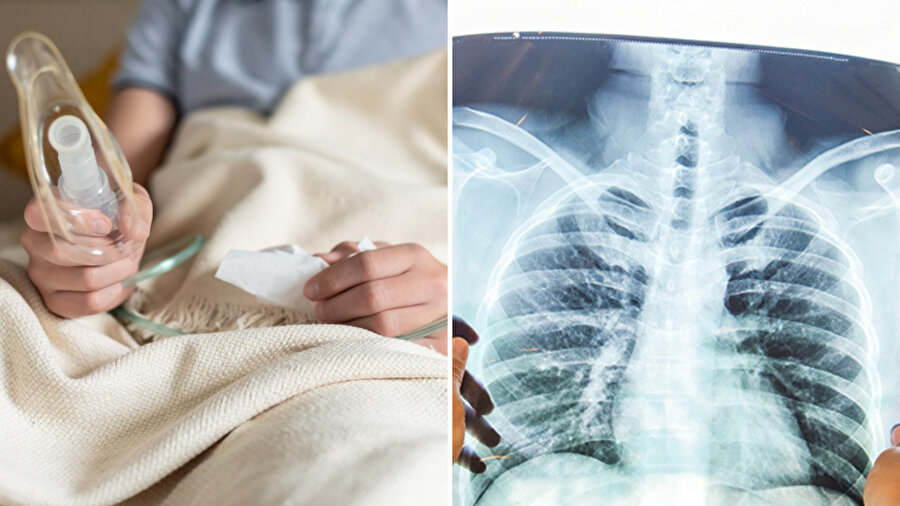

Kışla birlikte artan zatürre vakaları, sinsi bir tehlikeyi maskeliyor olabilir. Medipol Sağlık Grubu’ndan Prof. Dr. Cüneyt Saltürk ve Prof. Dr. Kemal Karapınar uyardı: Aynı bölgede tekrarlayan zatürre, aslında akciğer kanserinin habercisi olabilir. Özellikle sigara içenler ve yaşlılar, iyileşmeyen enfeksiyonlarda vakit kaybetmeden ileri tetkik yaptırmalı.

Kış aylarının gelmesiyle artışa geçen solunum yolu enfeksiyonları, görünmeyen bir tehlikeyi maskeliyor olabilir. Medipol Sağlık Grubu’ndan Göğüs Hastalıkları Uzmanı Prof. Dr. Cüneyt Saltürk ve Göğüs Cerrahisi Uzmanı Prof. Dr. Kemal Karapınar, özellikle yaşlılar ve sigara kullananlarda tekrarlayan zatürre vakalarının hafife alınmaması gerektiğini vurguladı.

Uzmanlar, aynı bölgede nükseden enfeksiyonların basit bir üşütmeden öte, akciğer kanseri veya bağışıklık sistemi hastalıklarının erken habercisi olabileceği konusunda uyararak ileri tetkik çağrısında bulundu.